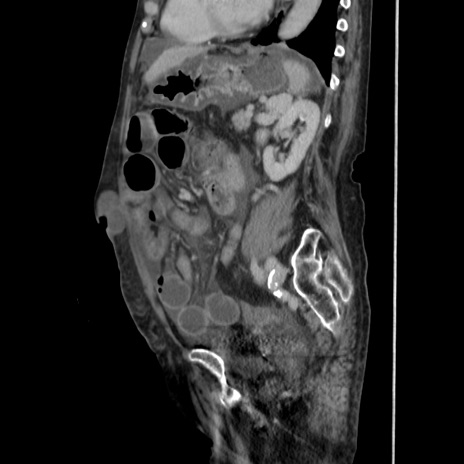

症例31(矢状断像)

【症例】80歳代 女性

【主訴】腹部膨満感

【現病歴】他院にて肝硬変にてフォロー中。1週間前から便秘、腹部膨満感、臍部腫瘤あり受診となる。

【既往歴】肝硬変

【身体所見】腹部膨隆あり、皮膚変化なし、疼痛なし。

【データ】WBC 4600、CRP 0.25